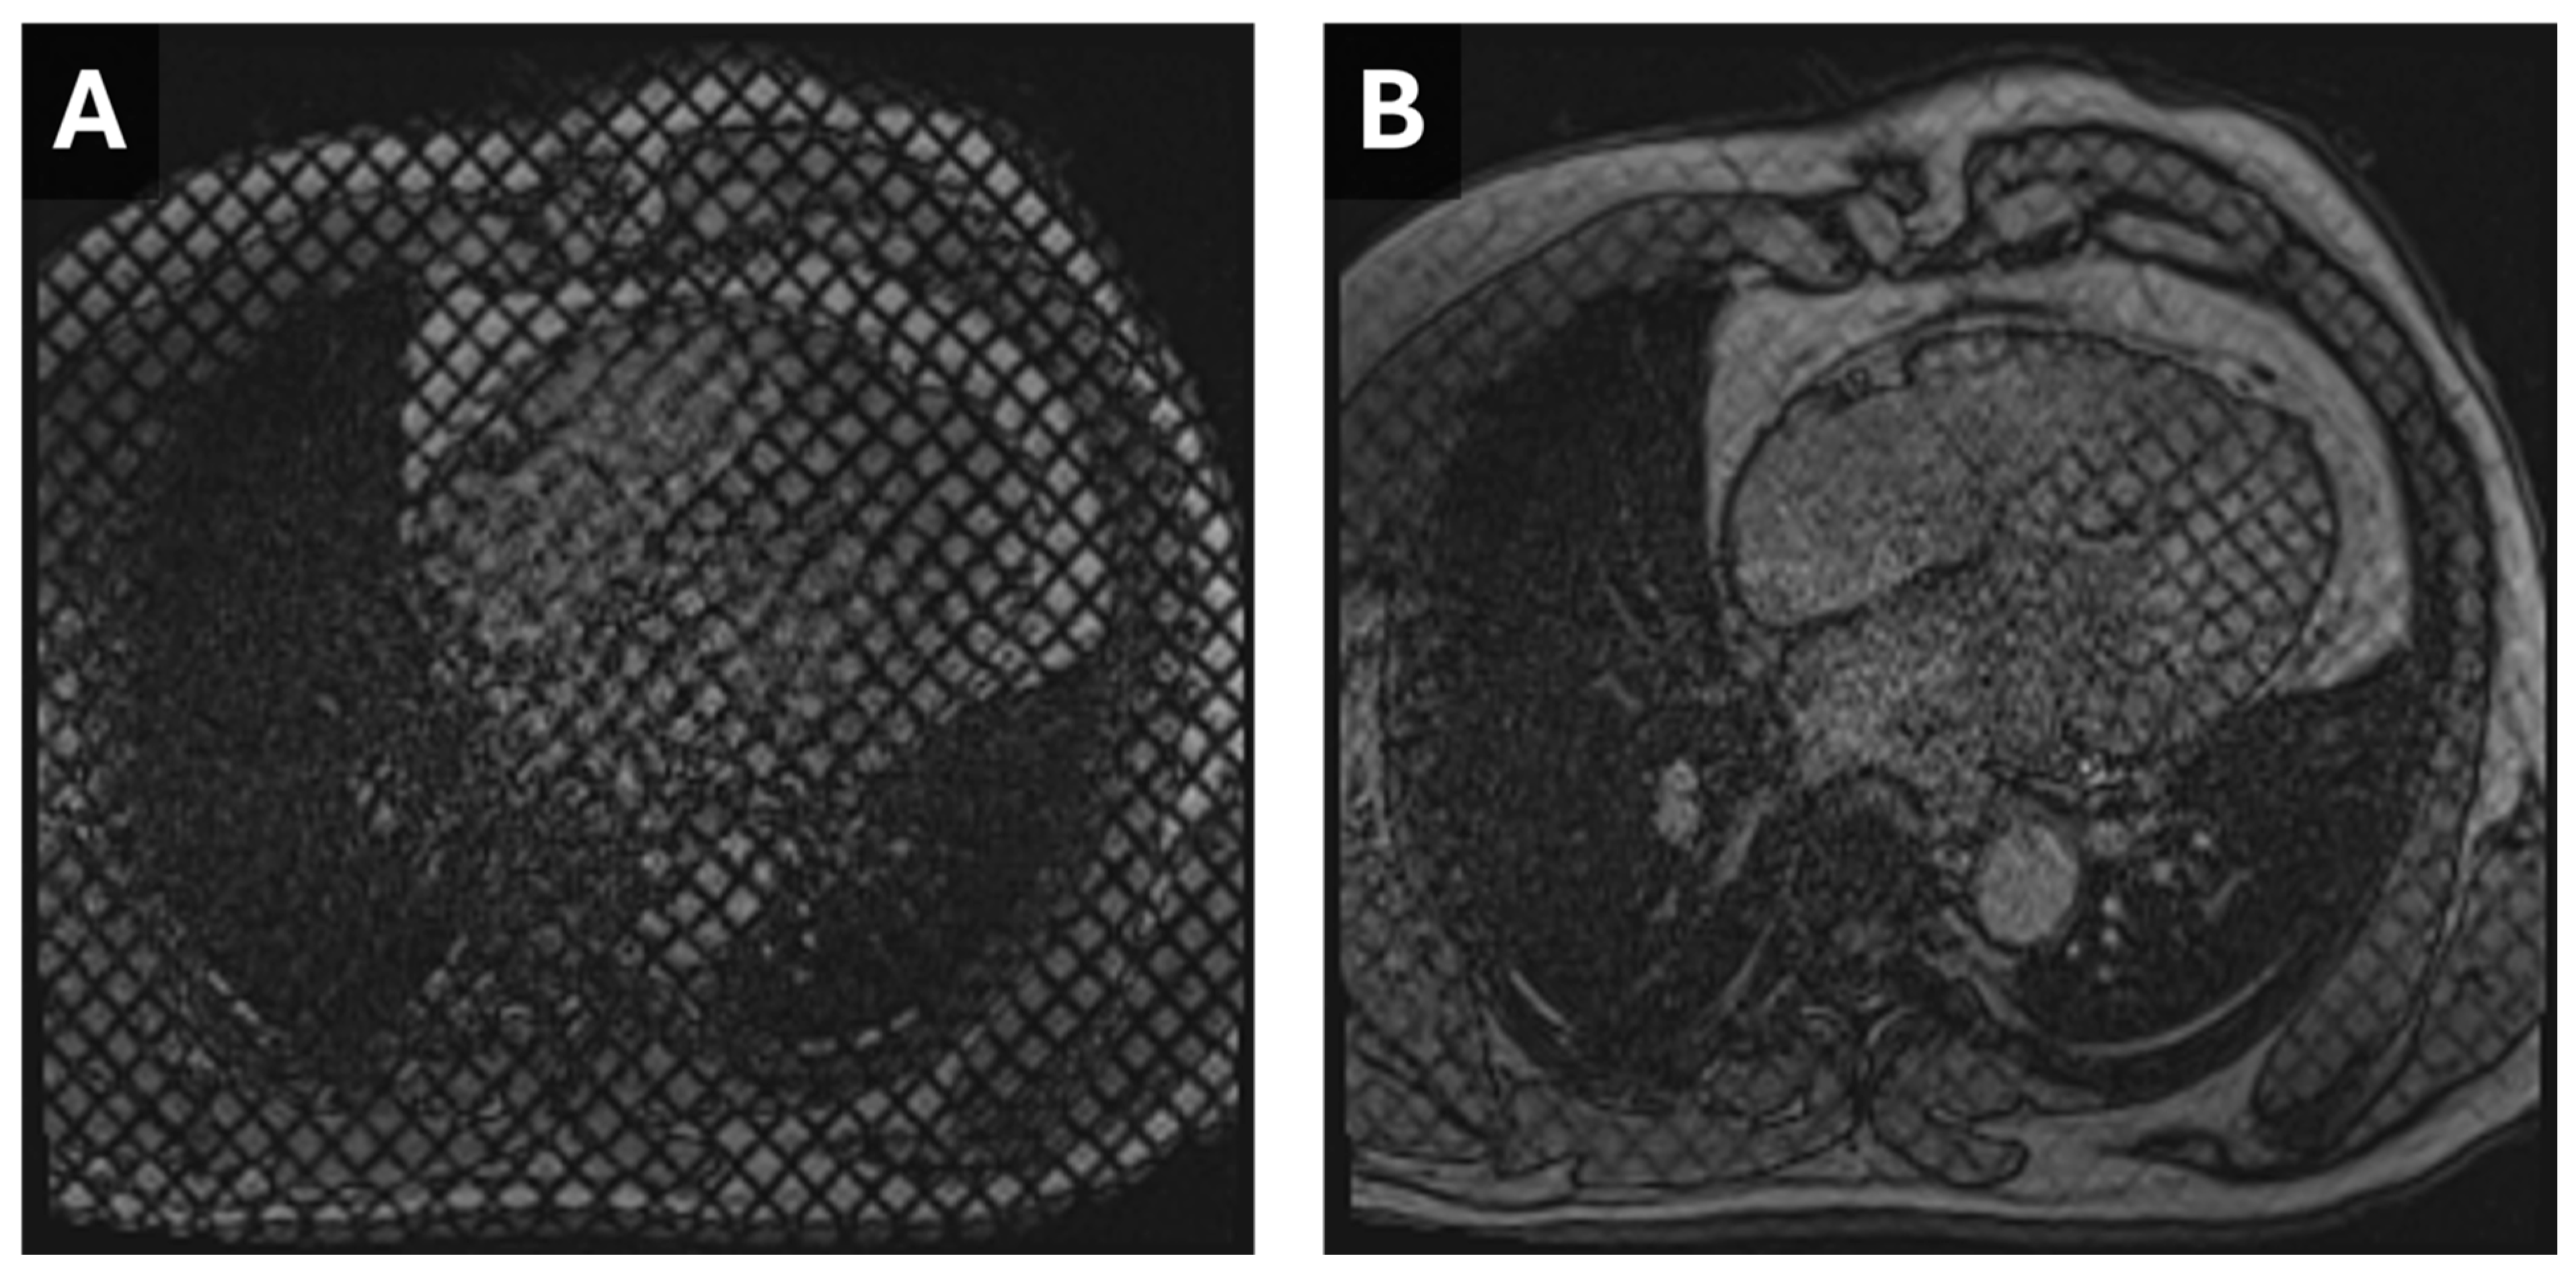

7. Arrhythmogenic Cardiomyopathy

- Venlet, J.; Tao, Q.; de Graaf, M.A.; Glashan, C.A.; de Riva Silva, M.; van der Geest, R.J.; Scholte, A.J.; Piers, S.R.D.; Zeppenfeld, K. RV Tissue Heterogeneity on CT: A Novel Tool to Identify the VT Substrate in ARVC. JACC Clin. Electrophysiol. 2020, 6, 1073–1085. [Google Scholar] [CrossRef] [PubMed]

- Conte, E.; Mushtaq, S.; Carbucicchio, C.; Piperno, G.; Catto, V.; Mancini, M.E.; Formenti, A.; Annoni, A.; Guglielmo, M.; Baggiano, A.; et al. State of the art paper: Cardiovascular CT for planning ventricular tachycardia ablation procedures. J. Cardiovasc. Comput. Tomogr. 2021, 15, 394–402. [Google Scholar] [CrossRef]